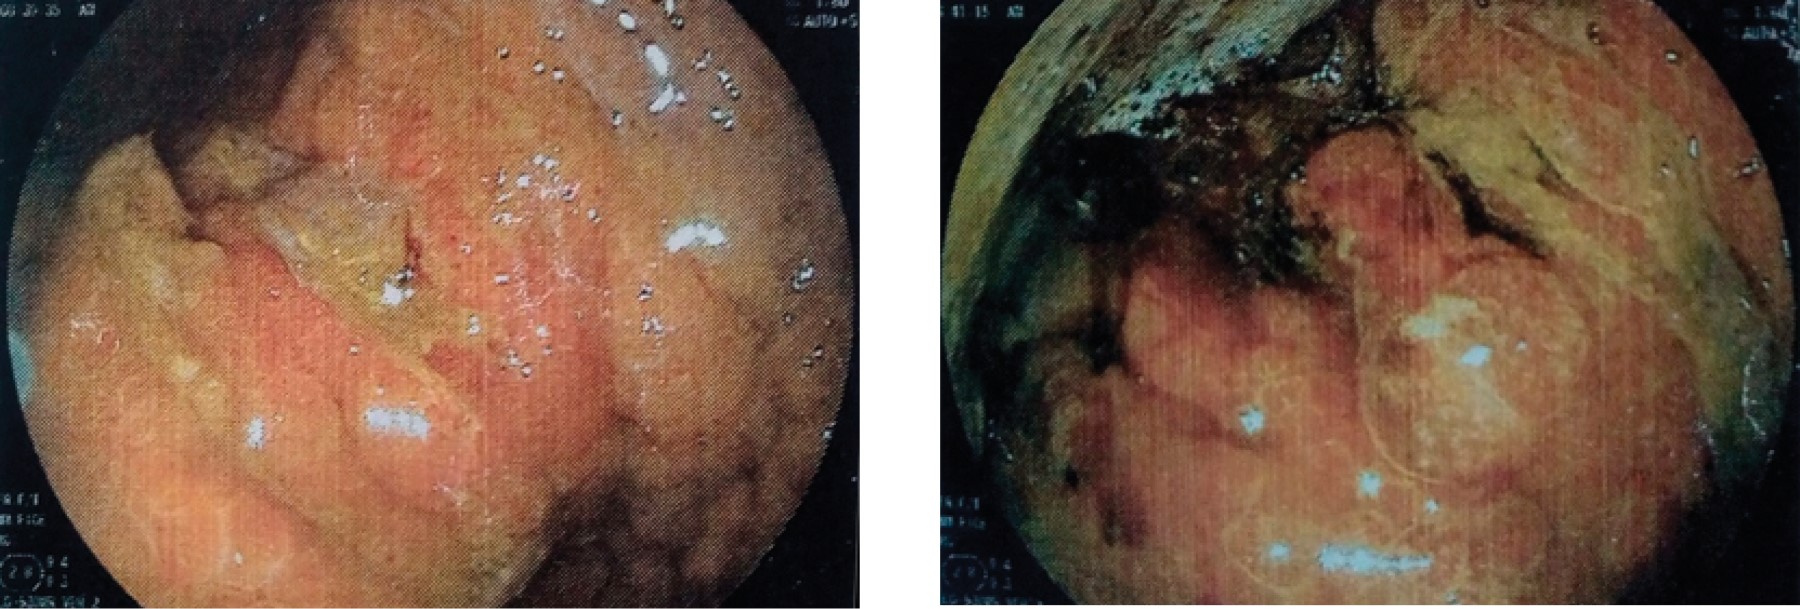

PRESENTACIóN DEL CASO

Figura 1

Figura 2